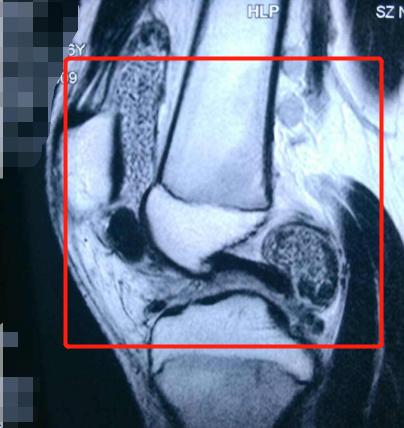

关节是非常复杂的,它的内部存在着各种软组织,而滑膜就是位于关节内的结缔组织膜。滑膜对于关节而言,有着非常重要的作用——它能分泌滑液,从而让关节更流畅地活动,提高关节的耐用性。

当滑膜受到刺激或者其它因素影响时,就可能"发炎"(滑膜炎症反应)——关节腔内的滑膜变肿胀,滑液分泌异常,最终形成"关节内积液",也就是很多患者朋友说的"关节积水"

(膝关节滑膜炎)